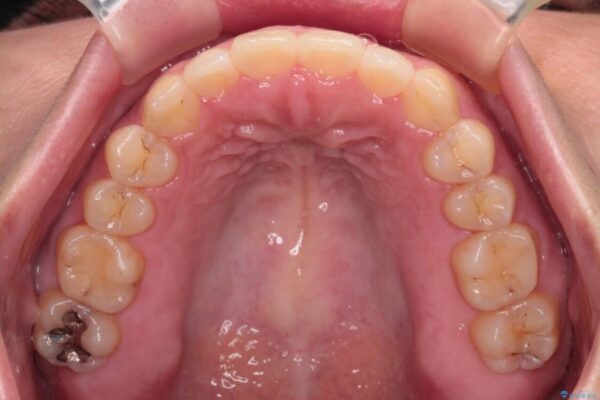

治療前

• 【モニター】カリエール・ディスタライザーを併用した八重歯のインビザライン矯正 治療前画像